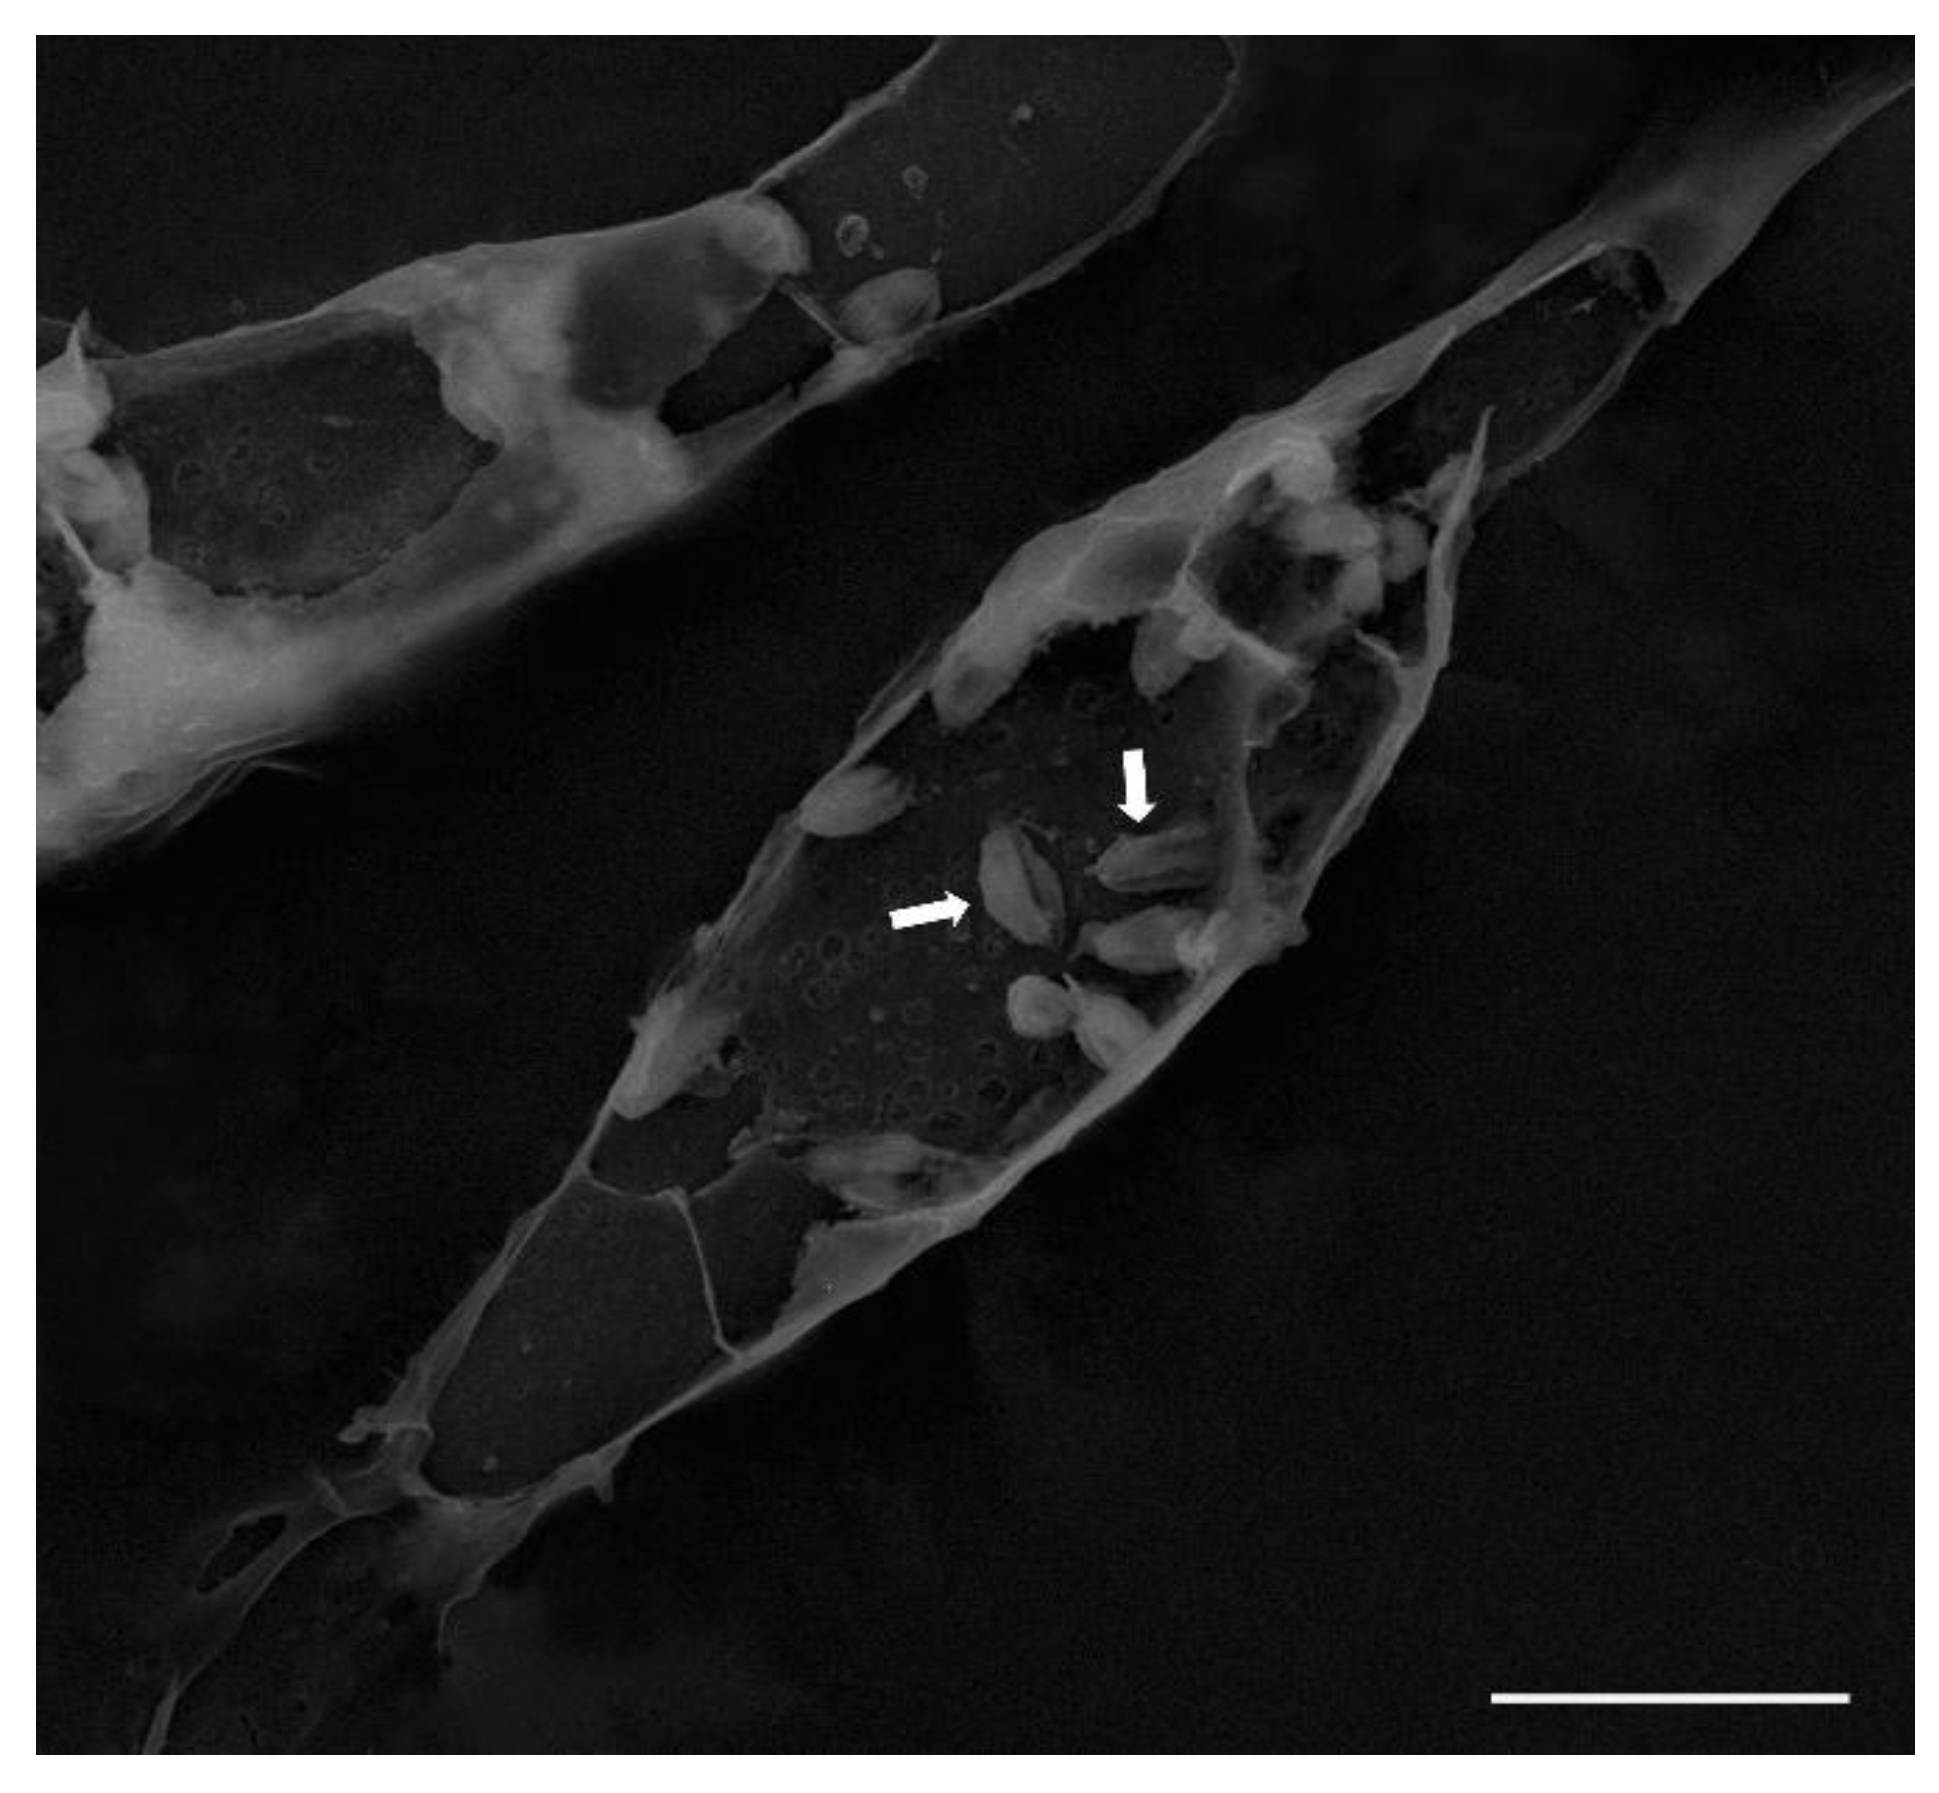

Giemsa staining confirmed amastigotes within parasitophorous vacuoles (Figure 2). SEM showed rounded intracellular forms with membrane protrusions (Figure 3).

Figure 3. Macrophage infected with Leishmania (L.) amazonensis, showing intracellular amastigote forms (arrows) visualized by scanning electron microscopy (SEM).